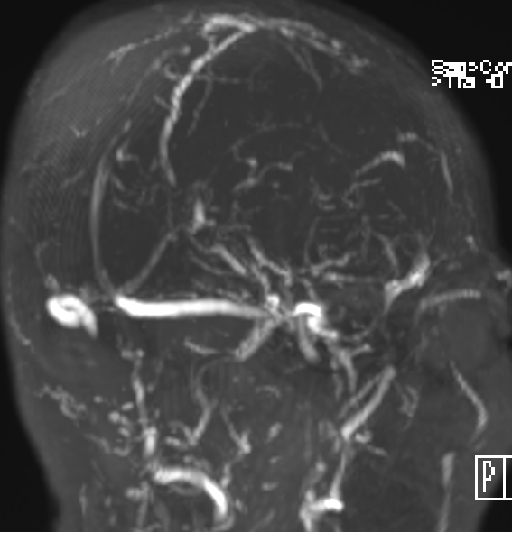

2015-1-30 DSA

脑压为60mm水柱

低颅压原因?(分流泵故障?脑顺应性差?

2015-2-1

在局麻下行腰椎穿刺术+ 测脑压术,患者取左侧卧位,测量脑脊液压力为60mm水柱。